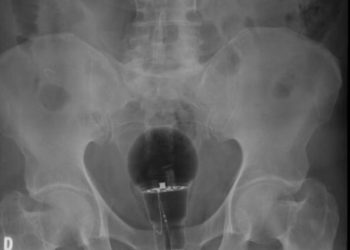

Tag: lâmpada no ânus